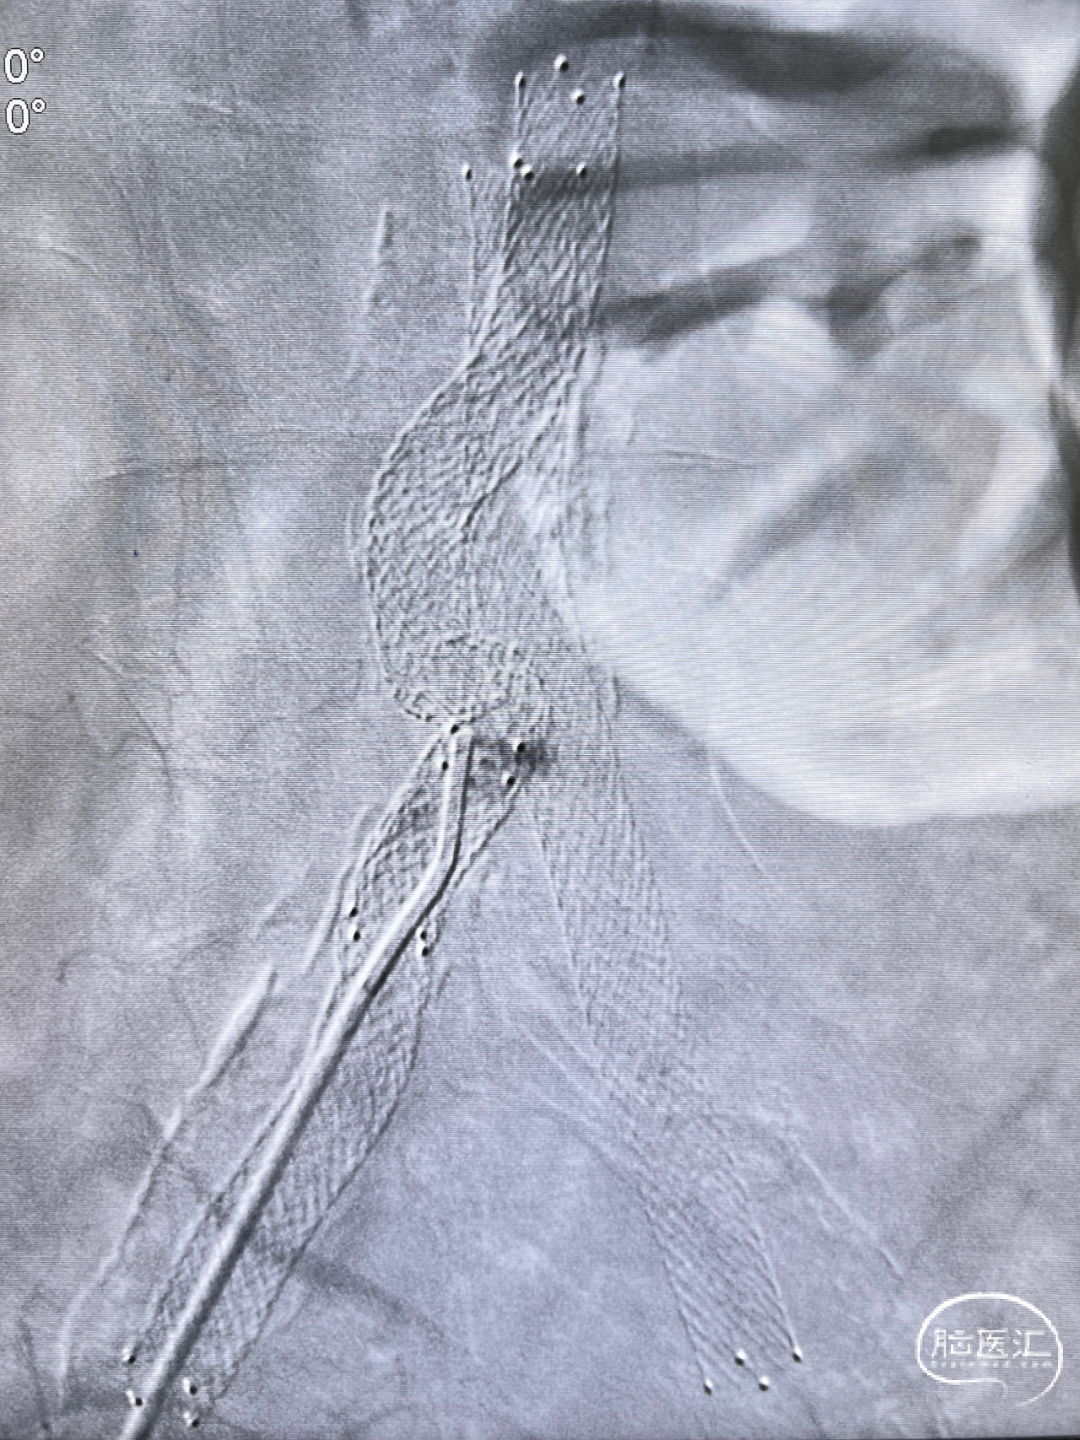

通路弓上系统稳定支撑, 8×40mm Precise自膨支架顺滑到位。

支架系统释放过程,系统稳定。

左侧颈内动脉正侧位造影,狭窄解除。